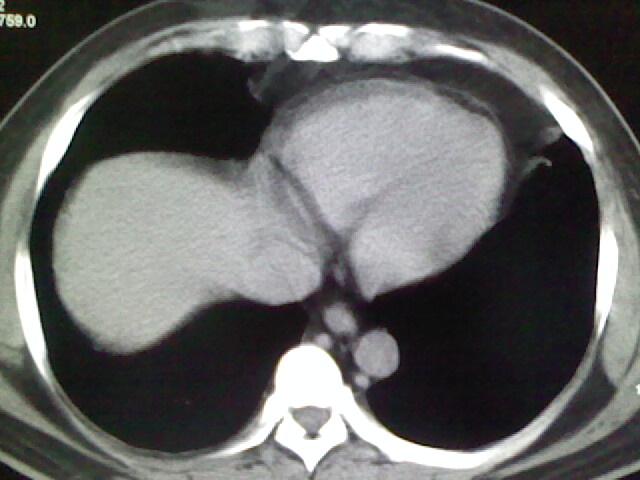

标题: CT17932:临床怀疑肺栓塞

男,34岁,自觉右侧胸痹,胸闷3天余

两肺纹理增多,余未见明确异常。

右侧肺动脉似见密度稍低影,请在机器的薄层上再看看有没有充盈缺损。